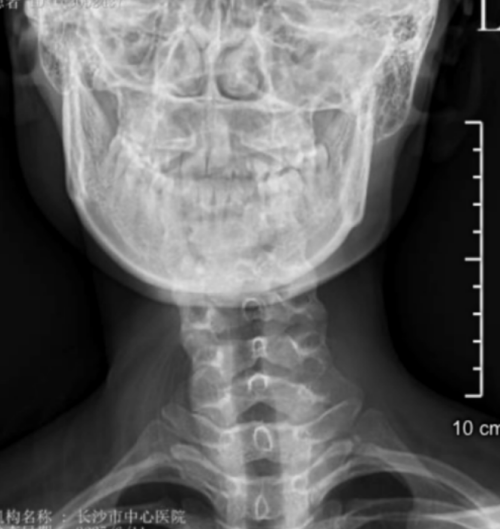

“患者属于典型的先天性肌性斜颈,由于延误治疗,颈部肌肉已形成纤维化改变。”该院脊柱外科二区主任、副主任医师曾浩介绍。面对这个特殊病例,医疗团队决定采用先进的微创技术——通过仅3厘米的切口,在放大数倍的手术视野下,精准松解挛缩的胸锁乳突肌,同时保护重要的神经血管。

与传统手术相比,这种微创方式具有显著优势:一是创伤小,切口仅为传统手术的1/3;二是恢复快,术后即可下床活动;三是更美观,采用美容缝合,疤痕几乎不可见。